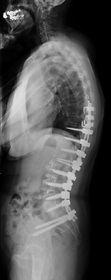

【術前】

第2, 第3, 第4腰椎に前方への変性すべりを認めます。痛みのため背中を反って立てないことが分かります。MRIではいずれの椎間でも強い脊柱管狭窄が発生し、神経が圧迫されているのが分かります。

【術後】

スクリューとロッド、人工骨を使用した手術により腰椎の階段状変性すべりが整復され、痛みが改善したため腰を反って立つことが出来ています。第2腰椎の前方すべりは軽微であったため、金属は使わず除圧術のみに留めています。